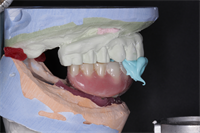

All on 6

Due to periodontal disease, all remaining dentition was extracted and six maxillary and four mandibular implants were placed and loaded simultaneously. A clear denture duplicate was used as a surgical guide and an alveolar reduction guide. This is the wax try in version to confirm...  Read More